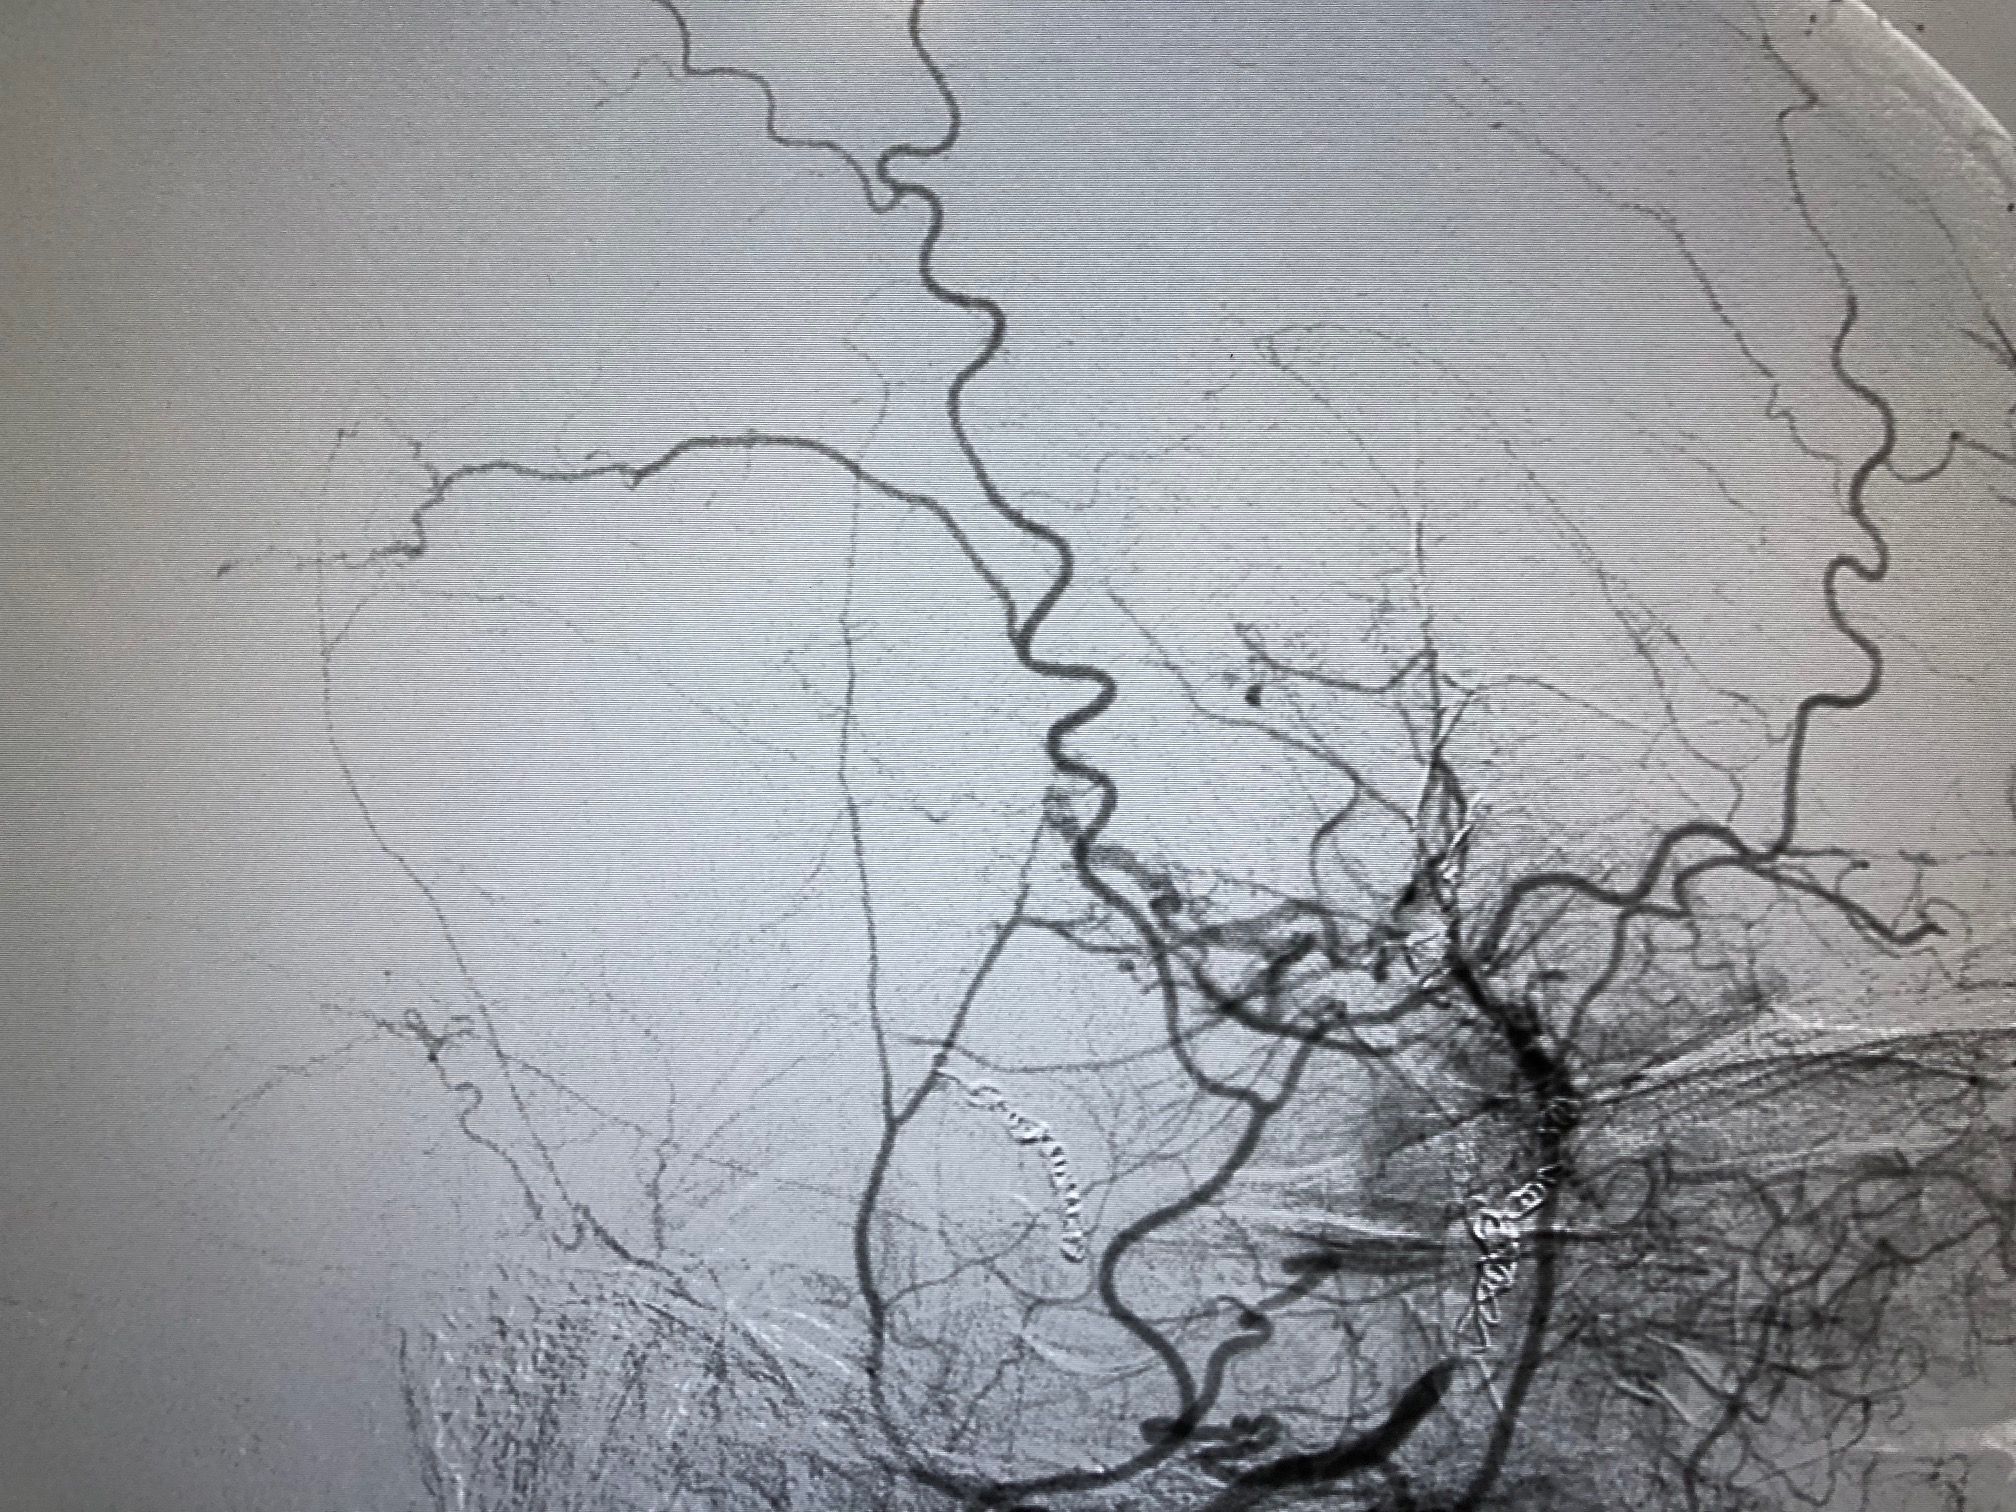

Angiography with preoperative embolization of the meningioma.

Preoperative angiography after embolization of the meningioma.